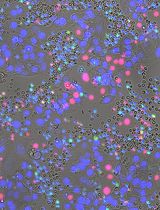

This protocol describes a novel technique to investigate the microcirculation dynamics underlying the pathology in the small intestine of neonatal mice using two-photon laser-scanning microscopy (TPLSM). Recent technological advances in multi-photon microscopy allow intravital analysis of different organs such as the liver, brain and intestine. Despite these advances, live visualization and analysis of the small intestine in neonatal rodents remain technically challenging. We herein provide a detailed description of a novel method to capture high resolution and stable images of the small intestine in neonatal mice as early as postnatal day 0. This imaging technique allows a comprehensive understanding of the development and blood flow dynamics in small intestine microcirculation.

In recent years TPLSM has become increasingly popular in in vivo research. However, intravital imaging of the small intestine in neonatal mice has been challenging due to their small body size and fragility of the intestinal wall. We have developed a novel application of TPLSM to visualize and study the small intestine of neonatal mice in vivo.

Our method allows for direct microvascular blood flow analysis. Stappenbeck TS et al. (2002) reported a method to analyze intestinal microcirculation indirectly from intestinal tissue samples harvested immediately after injecting fluorescein isothiocyanate-labeled dextran into the heart (Yu et al., 2009; Watkins and Besner, 2013; Yazji et al., 2013). However, thisand other similar methods for intravital imaging of the adult mouse intestine are not functional in blood flow dynamics. Our method allows for blood flow dynamics analysis, and facilitates investigation of intestinal villi development and establishment of the capillary network complexity (Stappenbeck et al., 2002). This protocol will allow the investigation of pathological processes associated with intestinal blood flow dynamics in vivo, thus promoting translational research.

The TPLSM imaging method described here can be easily applied to investigate different physiological processes in the neonatal intestine in multiple mouse models. For example, we are using this method to study blood flow dynamics and inflammatory responses in necrotizing enterocolitis (NEC), intestinal epithelium and micro-vasculature development in short bowel syndrome (SBS), inflammatory and immunological status in inflammatory bowel disease (IBD), and ischemia-reperfusion injury in midgut volvulus. Previous studies investigated neonatal intestinal microcirculation in experimental NEC ex vivo, however, these studies did not consider the effects of blood flow dynamics in capillary-vessels in the villi. Our new method allowed us to measure neonatal intestinal microcirculation from movies of live blood flow and to derive blood flow velocity, vessel diameter and inflammation, and assess irrigation of the serosal and mucosal layers. Moreover, this technique is being used to visualize and quantify live blood flow dynamics during reperfusion and ischemia in experimental midgut volvulus, which will be useful to identify the primary intestinal tissues affected.